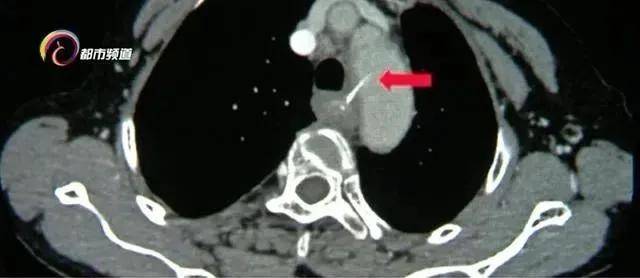

疼痛难忍的女士就医后 , 医生通过仪器发现这根鱼刺足有3厘米长 , 并且已经到了食管的位置 , 更危险的是 , 鱼刺已经穿破食管壁和胸主动脉内侧壁 , 随时可能导致大出血 。 正是之前多次吞咽的饭团 , 将鱼刺带到了这个"危险地带" 。

云南省第一人民医院消化内科主任 宋正己:“人体的食道大概25厘米长 , 有三个狭窄处 , 第一个狭窄处就是咽后壁和食管的结合部 , 这个地方绝大多数都可以在 , 耳鼻喉科用喉镜取出来 , 第二个狭窄就是在食道的中段这个位置 , 第二狭窄处是最危险的 , 它周围都是一些大的血管 , 人体内最粗的血管 , 胸主动脉 , 就紧邻在食道的第二狭窄处 。 ”